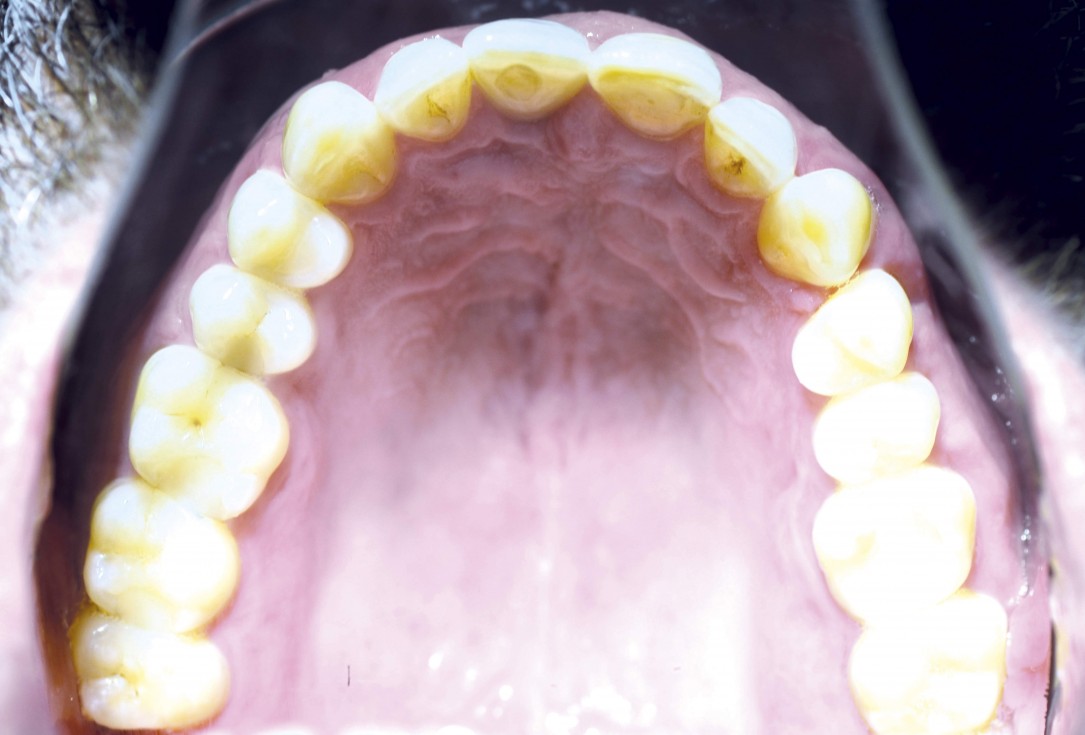

17/18 - Prosthetics 1 year after uncovering the implant – occlusal view

Block augmentation with maxgraft® and cerabone® – PD Dr. Dr. F. Kloss